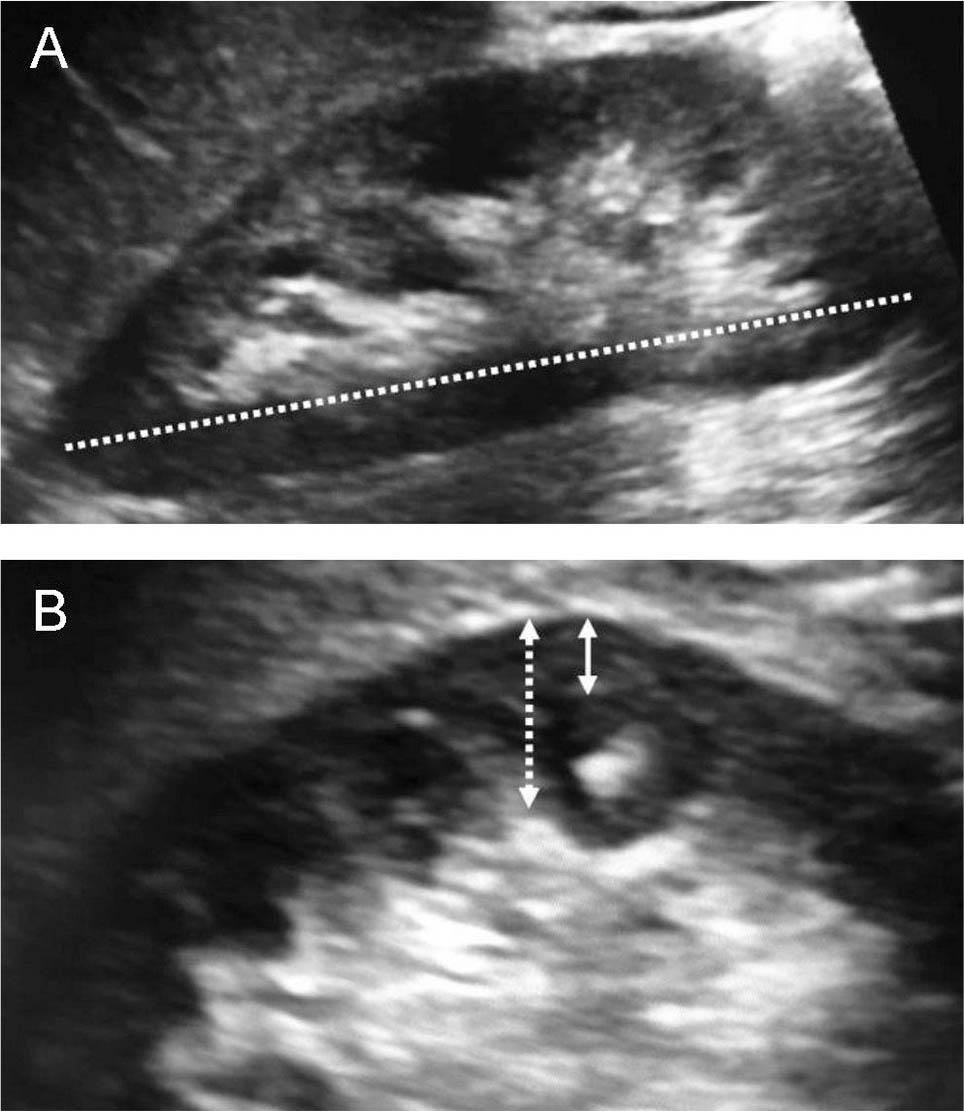

Figure 1